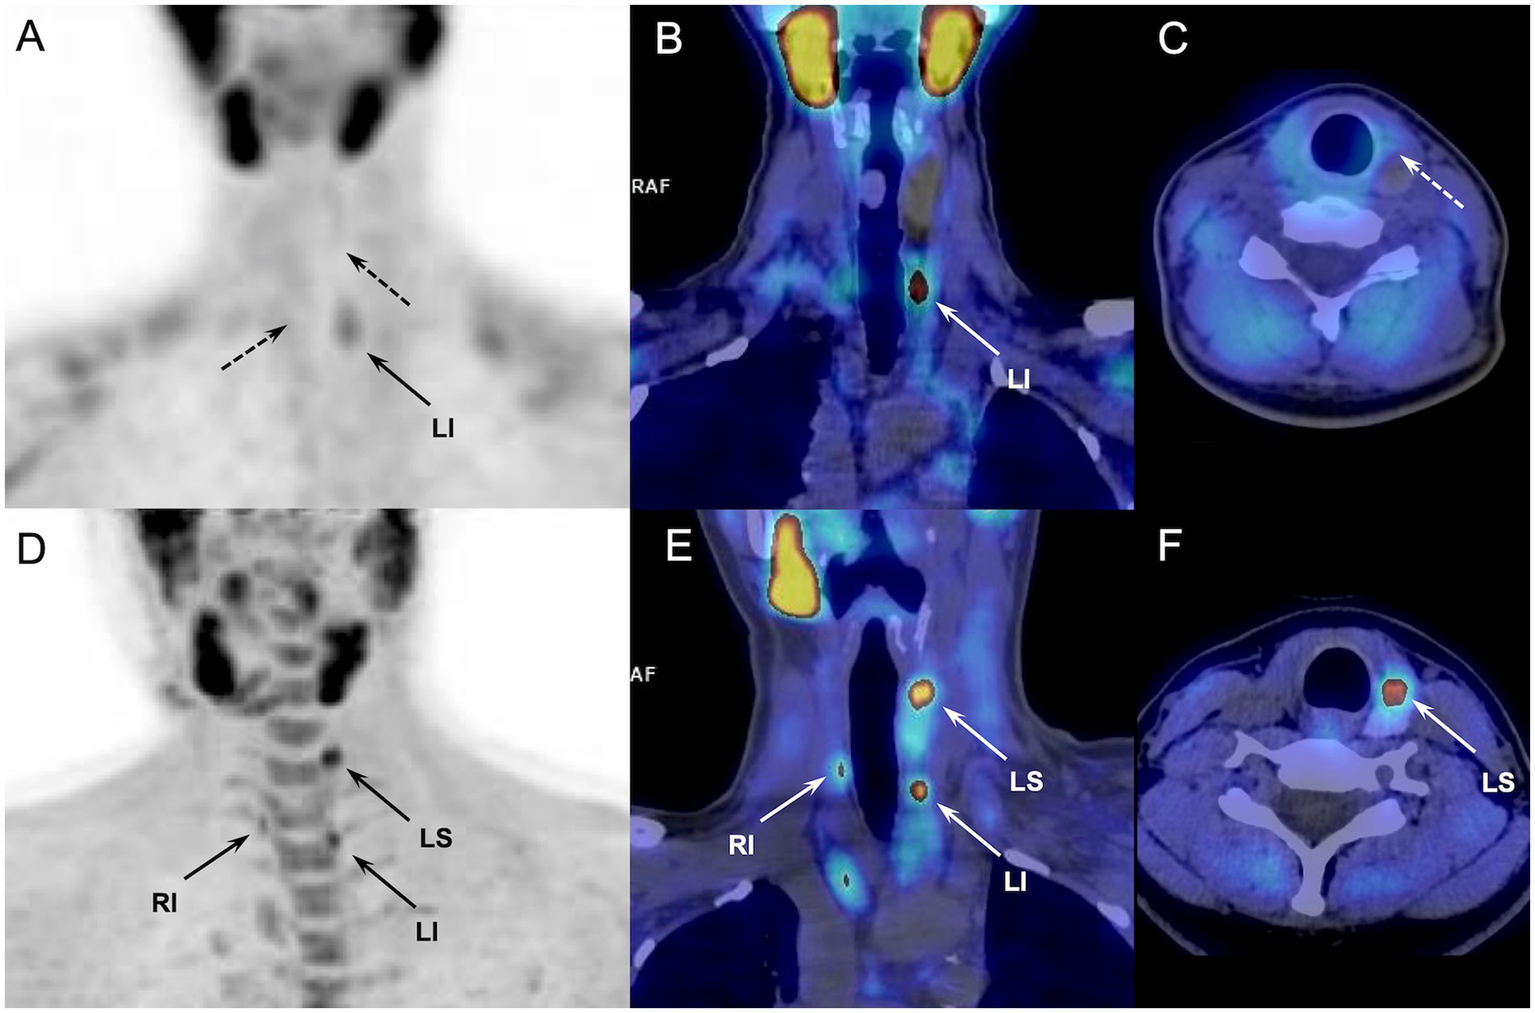

18F-FCH PET/CT identified nine pathologic parathyroids not detected by 99mTc-sestamibi scintigraphy in 8 out of 64 examined patients (12.5%) (Figure 1), allowing to detect four patients with MGD, and 1 ectopic gland. In all eight patients, parathyroid scintigraphy was performed according to the 99mTc-sestamibi/123I subtraction protocol. Moreover, 18F-FCH PET/CT allowed the reassessment of false-positive scintigraphic diagnosis (scinti+/PET-) for 8 parathyroids from 7/64 patients (11%). Only one hyperfunctioning gland in one patient was missed on 18F-FCH PET/CT and correctly identified by 99mTc-sestamibi scintigraphy. Neither pathological features nor hormone secretion or the patient’s clinical profile explained the discordant imaging results.

Figure 1

Discordant results of 99mTc-sestamibi parathyroid scintigraphy (upper panel, A-C) and 18F-FCH PET/CT (lower panel, D-F) (anterior MIP, coronal and axial fusion images) performed in a 62-y-old MEN patient with sporadic pHPT at primary staging (patient#12, Table 2). 18F-FCH PET/CT revealed a hyperfunctioning right inferior and left superior (in lower position) parathyroids (arrows), confirmed after surgery. 99mTc-sestamibi scintigraphy detected only the right inferior gland.